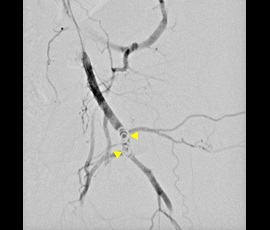

[血管系IVR] 動脈瘤 経動脈的コイル塞栓術

コイル挿入前